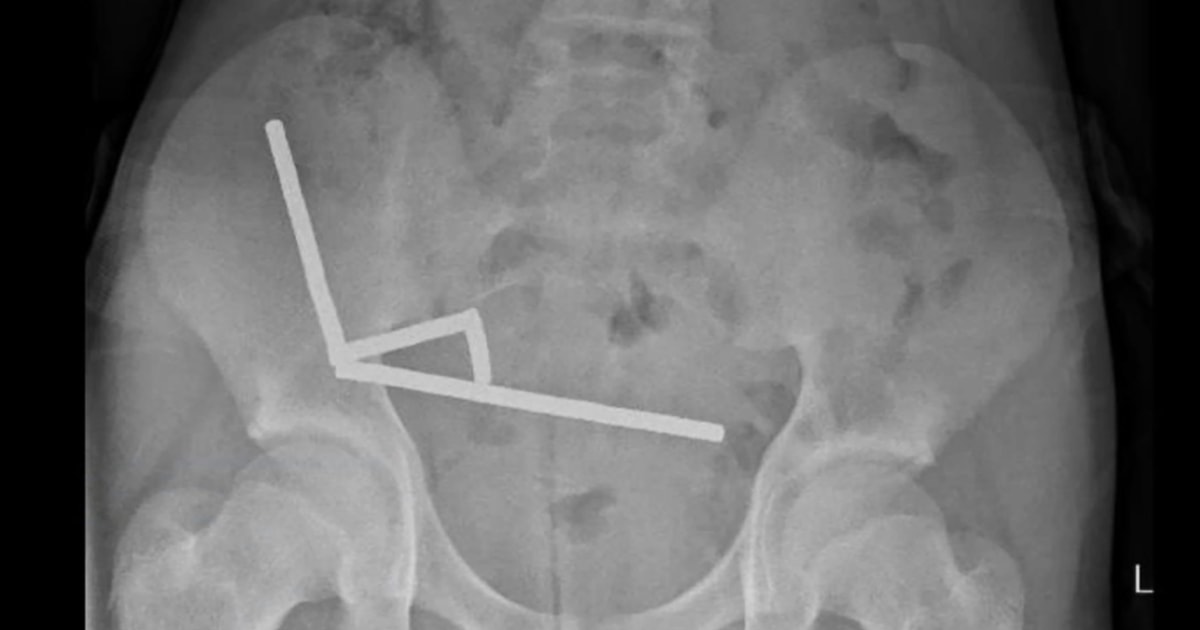

A boy who swallowed up to 100 high-powered magnets purchased online has undergone major surgery to remove them.

After four days of stomach pain, the 13-year-old boy was admitted to Tauranga Hospital on New Zealand’s North Island, where doctors…